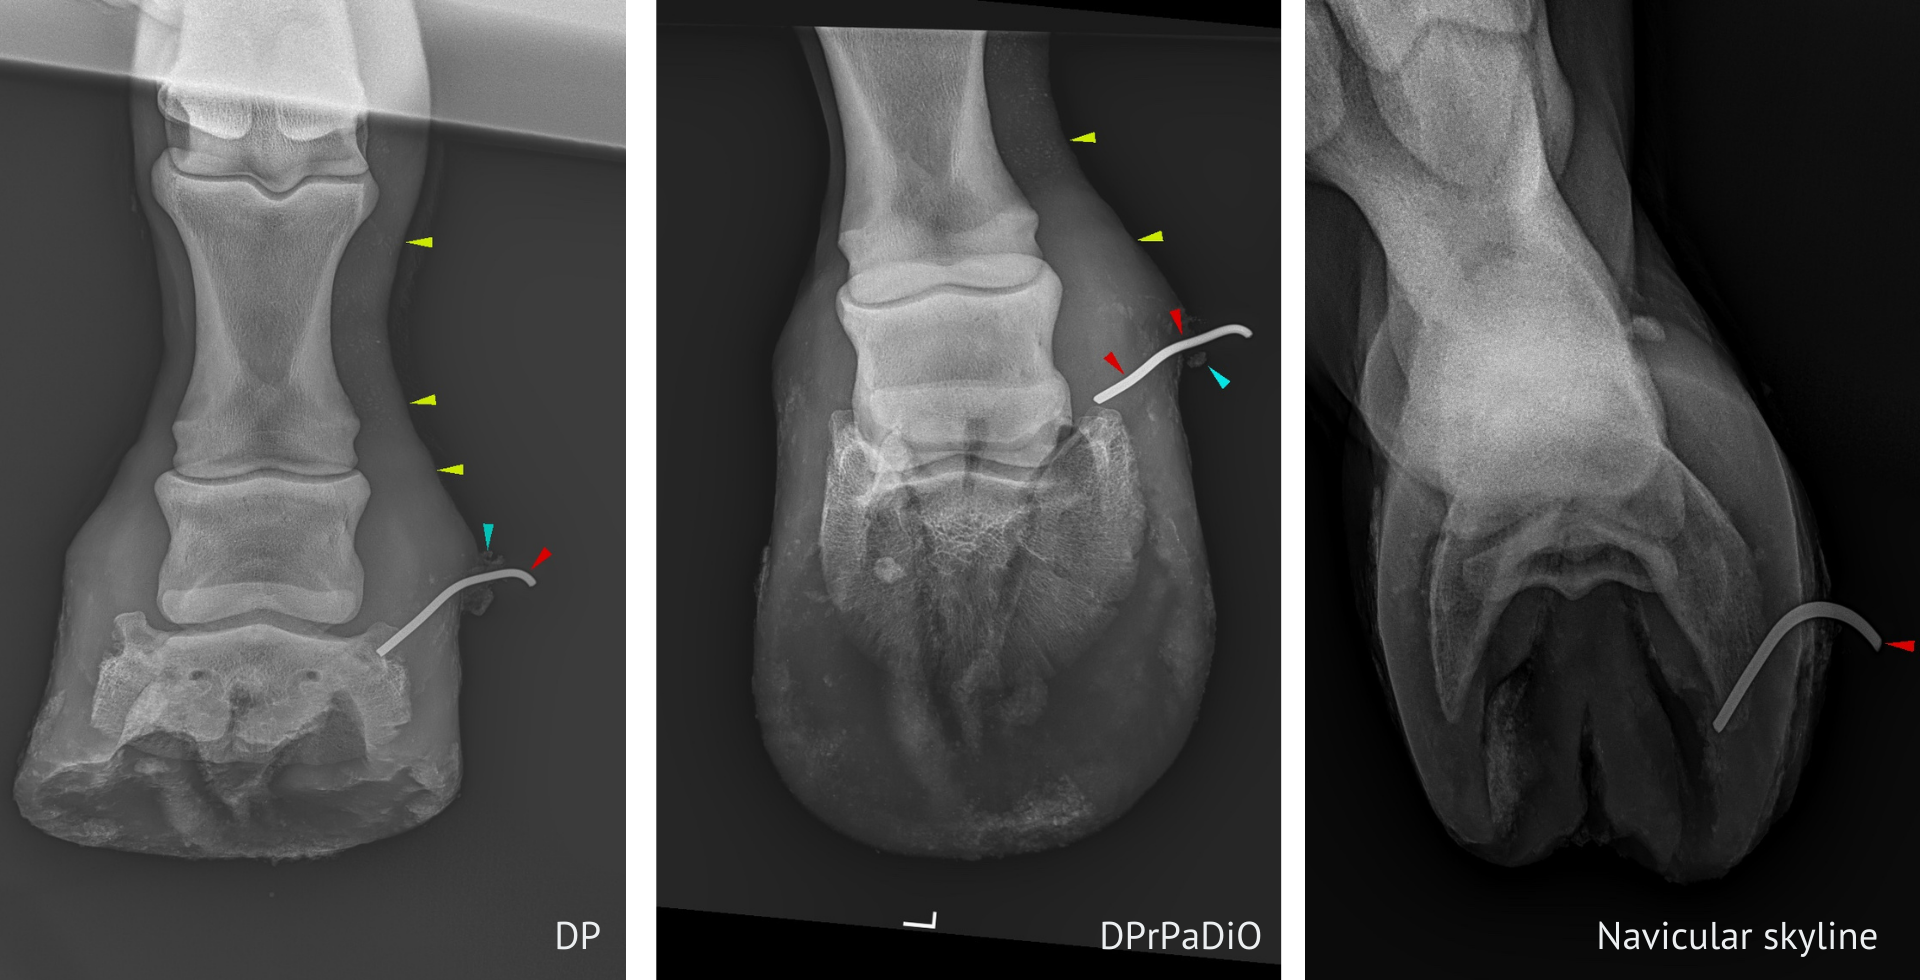

Equine Digital XRay at Fenton River Veterinary Hospital Tolland, CT Equine Quittor A condition once common in draft horses, particularly horses. Quittor is a term used to describe chronic infection of the medial or lateral collateral cartilage of the distal phalanx in the horse. The characteristic symptom is oozing, painful, open drainage tracts above the coronary band. Quittor is necrosis and infection of the lateral and collateral cartilage of the foot. Quittor. Equine Quittor.